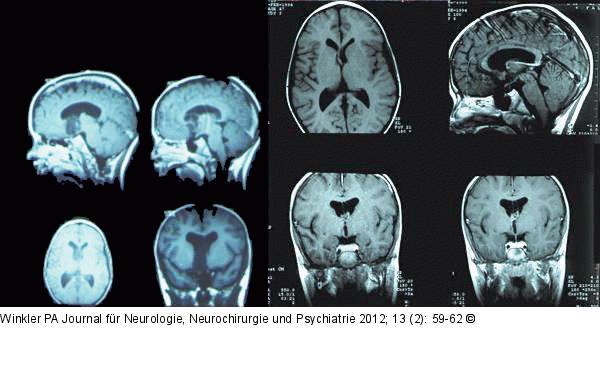

Abbildung 2: Gelastische Epilepsie Jahre alter Knabe mit „Pavor-nocturnus“-ähnlichen Anfällen und signifikanten kognitiven Einbußen vor der Operation. Diagnose: Gelastische Epilepsie (von γελαω = lache). Links präoperative Bilder, rechts postoperative Bilder. |

Abbildung 2: Gelastische Epilepsie

Jahre alter Knabe mit „Pavor-nocturnus“-ähnlichen Anfällen und signifikanten kognitiven Einbußen vor der Operation. Diagnose: Gelastische Epilepsie (von γελαω = lache). Links präoperative Bilder, rechts postoperative Bilder. |